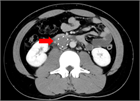

病態

1. 急性肺塞栓症とは、静脈系にできた塞栓子(大部分が血栓)が肺動脈を閉塞させ、その結果、肺動脈の血流が障害されて呼吸や循環に異常を来した状態をいう。